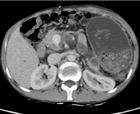

术后1月CT

血栓陈旧无法完全溶解,但因选择性贲周血管离断术保留了冠状静脉,门静脉血流可以通过食管下端交通支返流,无腹水等并发症发生。